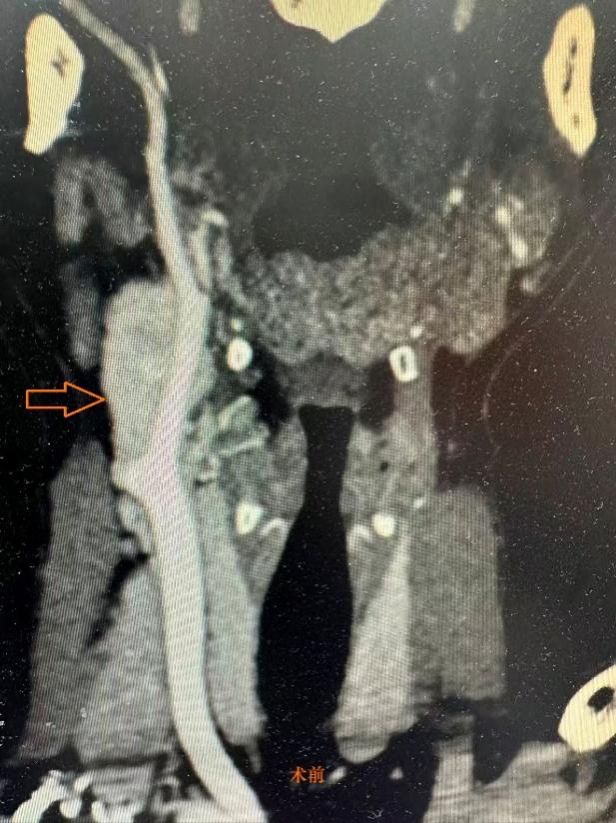

该患者因颈部出现无痛性肿物数月,遂来二附院就诊。接诊后,科室为其完善彩色多普勒超声、颈部CT及MR等相关检查,结果显示:肿瘤位于颈动脉分叉处,包绕部分颈内、颈外动脉血管结构,结合临床特征确诊为颈动脉体瘤(ShamblinⅡ型),此类肿瘤与颈动脉血管关系紧密,手术风险很高。

手术在任晓勇主任现场指导,许映龙副主任医师主刀,郭立主治医师、张楚彤医师、张勇麻醉师及手术室黄新坤和王泽宇等护理团队密切配合下顺利实施。术中探查发现,肿瘤位于颈总动脉分叉处,体积较大,肿瘤与颈外动脉之间的粘连程度明显重于术前影像学评估,肿瘤包绕血管并形成致密纤维性粘连,同时肿瘤周围存在丰富而复杂的供血血管网。在分离过程中,部分滋养血管破裂,出现较为迅猛的出血情况,手术团队迅速启动预设方案,采取精准止血及血流控制措施,同时为患者输注红细胞悬液2U以维持循环稳定。面对复杂的解剖关系和术中出血风险,团队协作,精细操作,最终成功将肿瘤完整切除,颈内、颈外动脉血流恢复良好,重要神经结构完好无损,手术顺利完成。